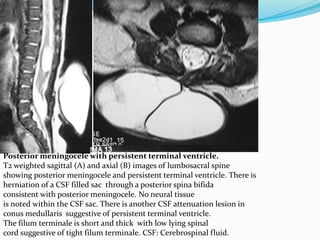

Posterior meningocele with persistent terminal ventricle.

T2 weighted sagittal (A) and axial (B) images of lumbosacral spine

showing posterior meningocele and persistent terminal ventricle. There is

herniation of a CSF filled sac through a posterior spina bifida

consistent with posterior meningocele. No neural tissue

is noted within the CSF sac. There is another CSF attenuation lesion in

conus medullaris suggestive of persistent terminal ventricle.

The filum terminale is short and thick with low lying spinal

cord suggestive of tight filum terminale. CSF: Cerebrospinal fluid.